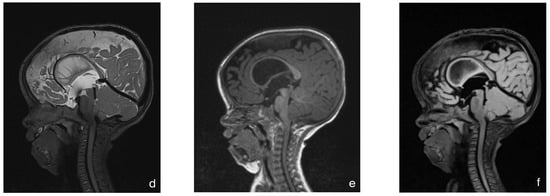

With this standardized procedural sedation approach and continuous multimodal monitoring, none of the patients required endotracheal intubation or a laryngeal mask airway. All MRI scans were reviewed by a board-certified pediatric radiologist and deemed of sufficient quality for diagnostic purposes. No repeat imaging was required due to motion artifacts. Figure 2 presents a representative MRI image acquired under the standardized sedation protocol.

Figure 2.

MRI of an 8-month-old child with achondroplasia. (a) Sagittal T2-weighted magnetic resonance image (MRI) shows foramen magnum stenosis with normal signal in the cervical spinal cord. (b) Sagittal T2-weighted MRI highlights a reduced dens–opisthion distance, with the anteroposterior diameter at the C2–C0 level measuring 9 mm. (c) Axial T2-weighted MRI shows ventriculomegaly. (d) Sagittal T2-weighted SPACE image demonstrates reduced perimedullary cerebrospinal fluid (CSF) flow void signal at the cervicocranial junction. (e) Sagittal T1-weighted image shows no evidence of cerebellar tonsillar herniation. (f) Sagittal T2-weighted FLAIR image shows no signs of cervical myelopathy.